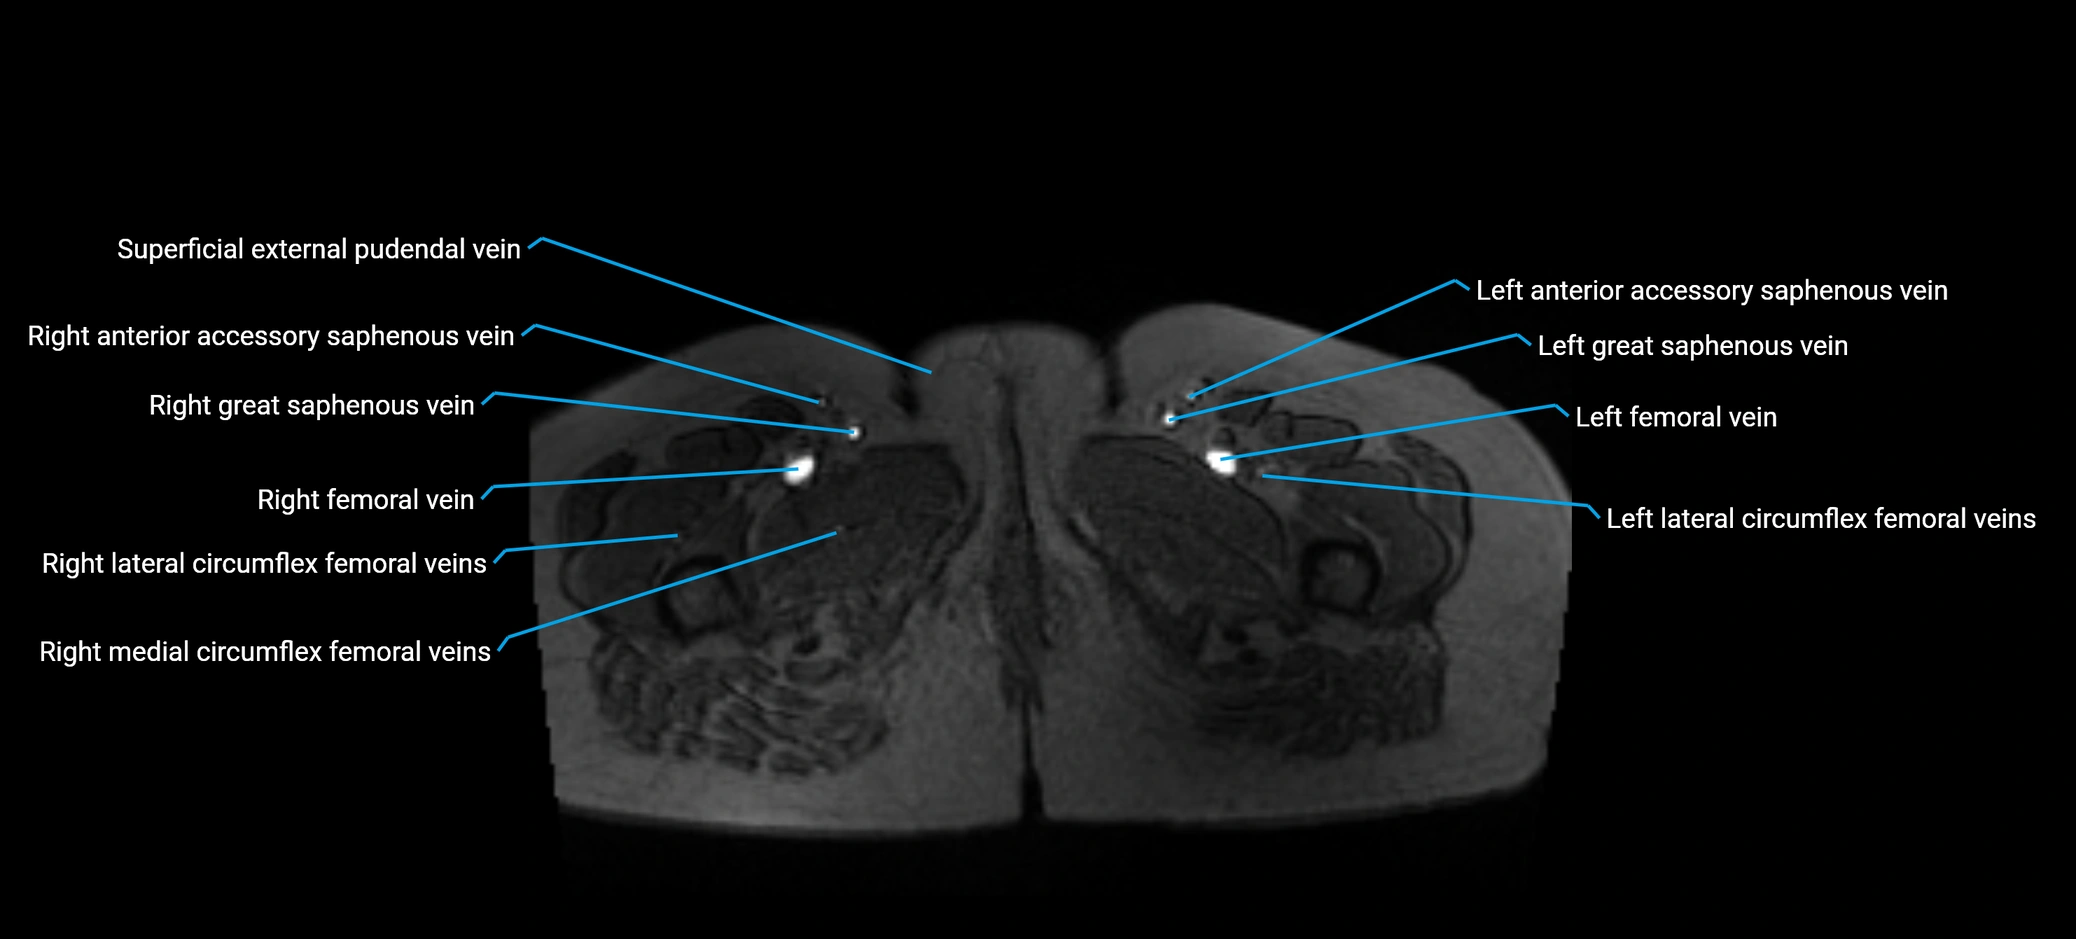

MRI image

image